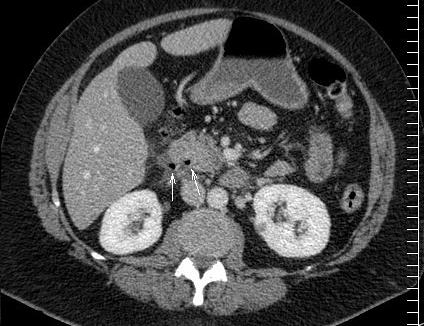

Perforation ulceres duodenale ( face

anterieure ) . Image de air libre a espace

superieure de l'abdomen . |

Ulcer de la face posterieure duodenum

perfore . Image de bulbe d'air extravation

exterieure justalesionelle ( fleche blanche )

. Image TDM en coupe axiale . |